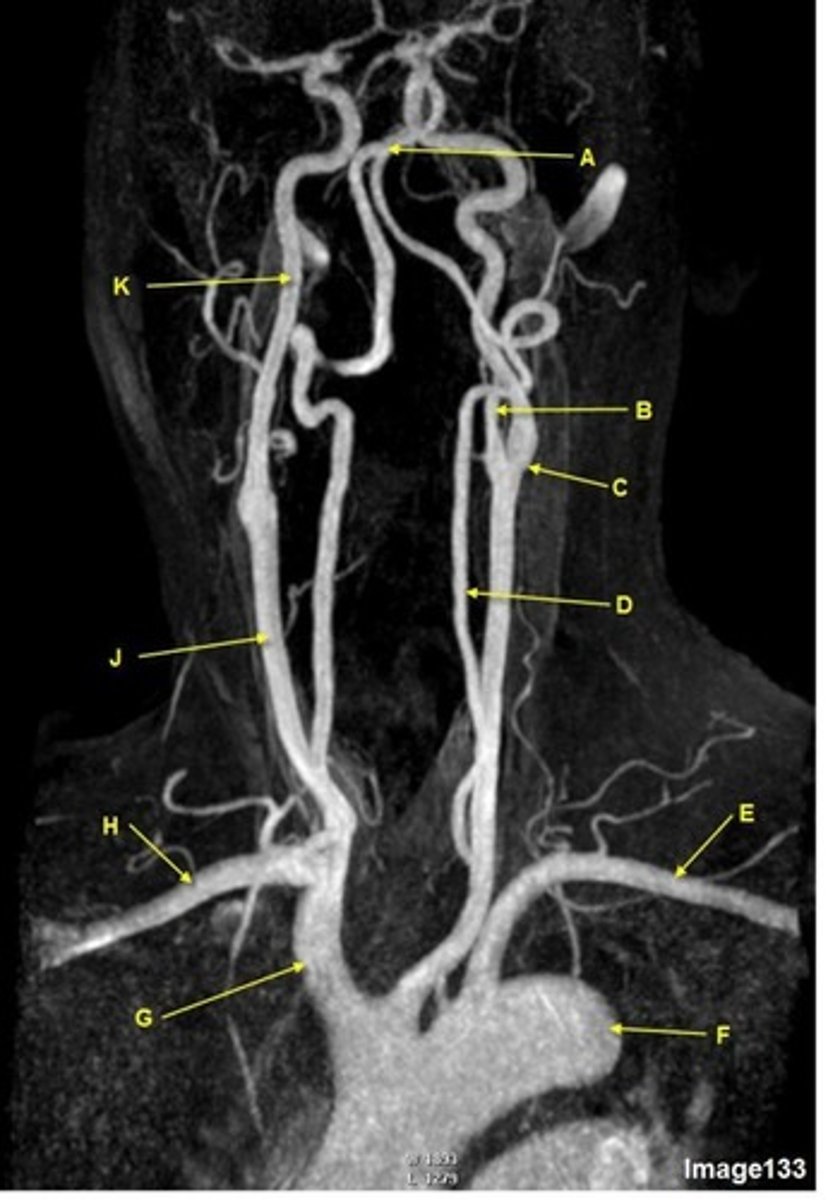

A, where does it supply blood to?

external carotid artery

face

B, where does it supply blood to?

internal carotid artery, anterior brain

C

Common carotid bifurcation

D

common carotid artery

E, where does it supply blood to?

vertebral artery, posterior brain

what kind of image is this?

MRA extracranial circulation

G

brachiocephalic trunk, innominate artery

H

R subclavian artery

K

internal carotid artery